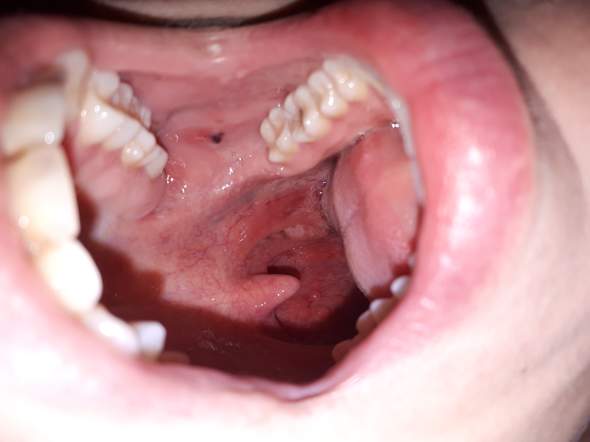

Sschwarzer Fleck An Innenbacke Mit Krassen Halsschmerzen Gesundheit Und Medizin Hno Schwellung